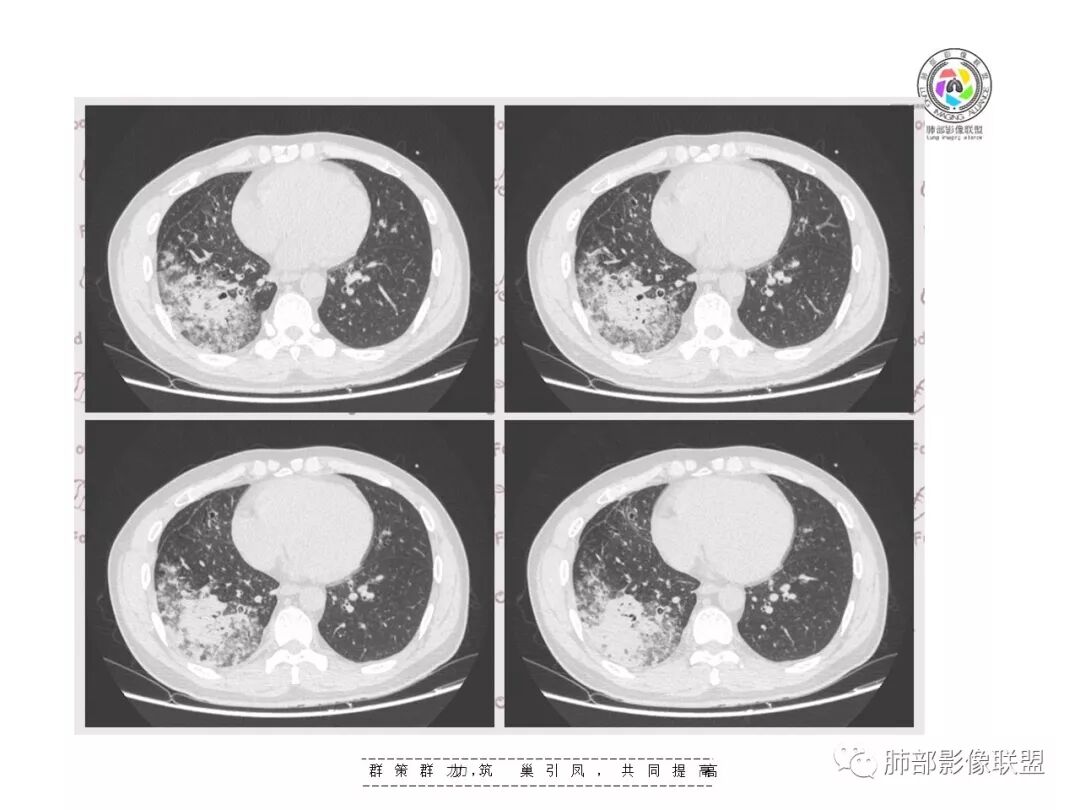

【影像资料】

张帅,首医附属潞河医院呼吸科:右肺下叶支气管开口明显狭窄,外基底段远端实变,内可见支气管征,周围可见弥漫结节样变,周围毛玻璃影,小叶间隔增厚,部分支气管壁不规则增厚,部分肺野可见小囊性变,壁部分增厚,右肺门明显增大,病灶与胸膜脂肪间隙增大,考虑恶性病变,腺癌。

王秀仙东宁市第二人民医院影像科:晨读:右肺下叶实变及磨玻璃影,边缘有收缩有膨隆,部分支气管进入扭曲扩张,磨玻璃影边缘清晰,实变影明显强化,内可见血管造影征,纵膈及肺门淋巴结肿大并强化,考虑粘液腺癌。

登封市三康医院(刘权威):右下肺肺不张,磨玻璃影,边缘清楚,空气支气管征,增强有强化,纵膈及右肺门淋巴结肿大并强化,考虑恶性肿瘤,粘液腺癌可能。

下叶外基底段为主实变,周围GGO

这个病灶很有特色

分布:沿支气管段、亚段朝外蔓延分布

实变+GOG

实变区边缘收缩,支气管走形自然

但是我们也可以看到实变区很多地方没看到支气管,也就是支气管在实变区分布不均匀,提示有些地方支气管腔内有物质填塞,显示不清

GGO边界大部分不清楚,内有树芽征,中央间质均匀增厚